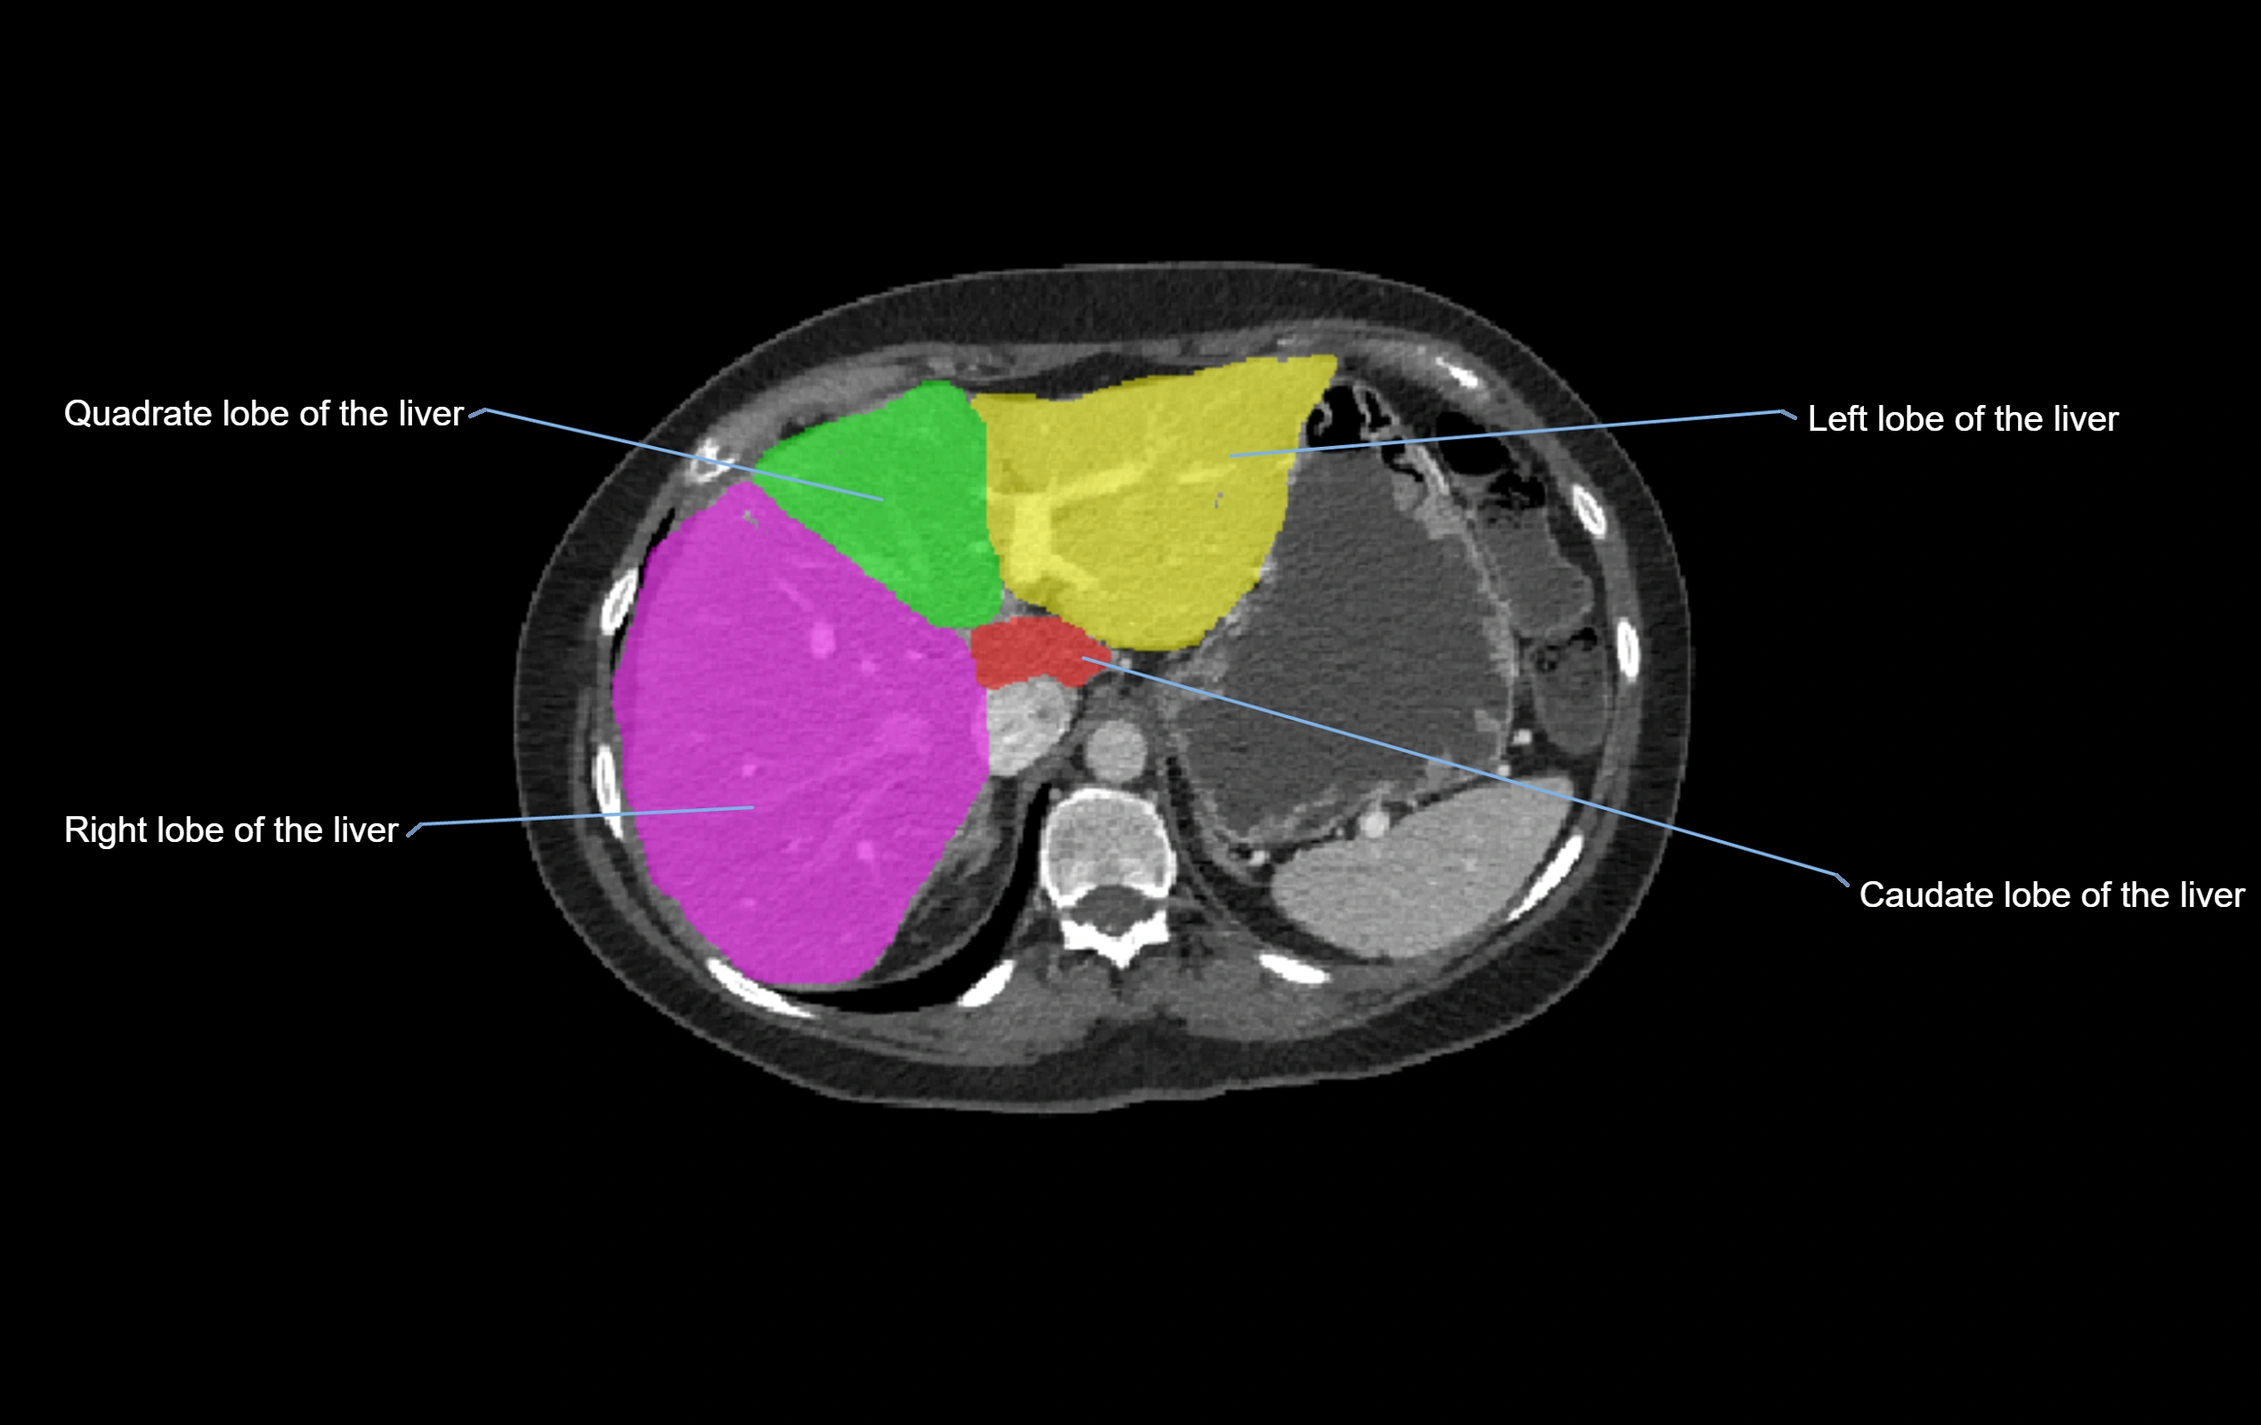

The caudate lobe of the liver is a distinct anatomical subdivision of the liver, designated as segment I in Couinaud’s classification. It lies on the posterior surface of the liver, between the fissure for the ligamentum venosum (left boundary) and the groove for the inferior vena cava (IVC) (right boundary). Superiorly, it is related to the posterior liver surface, and inferiorly it is separated from the left lobe by the porta hepatis.

The caudate lobe is unique because it receives dual portal venous and arterial inflow from both the right and left portal veins and hepatic arteries. It also has independent venous drainage directly into the IVC via multiple small hepatic veins, unlike other lobes that drain through the three main hepatic veins.

This anatomical autonomy makes the caudate lobe especially significant in liver surgery, transplantation, and hepatic venous outflow obstruction syndromes (e.g., Budd–Chiari syndrome). Enlargement of the caudate lobe is a characteristic imaging feature in chronic liver disease and cirrhosis.

CT Appearance

CT Pre-Contrast:

• Caudate lobe appears as a soft-tissue density, isodense to the rest of the liver

• Enlargement may be appreciated in cirrhosis or Budd–Chiari syndrome

CT Post-Contrast:

• Homogeneous enhancement in the portal venous phase, similar to rest of liver

• Independent venous drainage into the IVC may be visualized

• Lesions follow characteristic CT enhancement patterns (HCC: arterial hyperenhancement with washout; hemangiomas: peripheral nodular enhancement with centripetal fill-in)

CT Venous Phase (functional significance):

• Caudate lobe often enhances relatively more than other lobes in Budd–Chiari syndrome, due to preserved venous outflow

CT Image

image